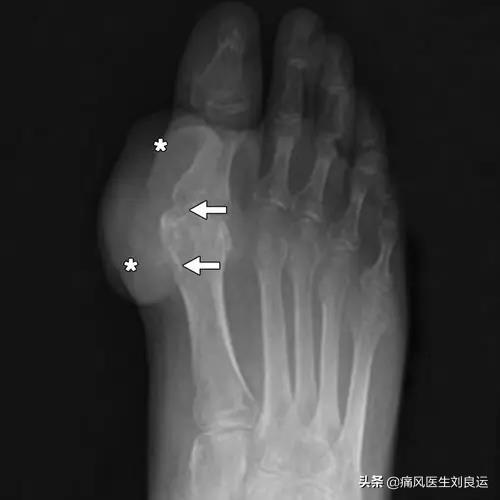

La deuxième étape consiste à effectuer une étude d'imagerie, par exemple pour détecter un "signe de double piste" sur l'échographie ou pour effectuer un "signe de double piste" sur l'échographie.La tomodensitométrie à double énergie révèle des dépôts d'urateetc., puis ouLes radiographies révèlent un gonflement des tissus mous, une destruction des bords du cartilage et une irrégularité des surfaces articulaires.!

- (10) Tuméfaction intra-articulaire asymétrique (confirmée par radiographie)

- (11) Kyste sous-cortical de l'os sans érosion osseuse (confirmé par radiographie)